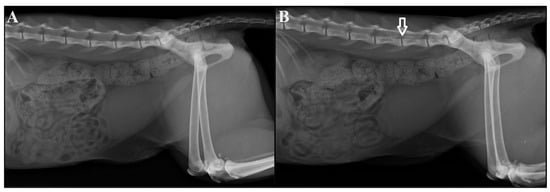

- Ramos, S.M.L.; Da Nóbrega Neto, P.I.; Ramos, C.T.C.; Marinho, P.V.T.; Ferreira, M.A.A.; De Melo, S.R.A. Epidurografia lombossacra com diferentes volumes de iohexol em felinos [Lumbosacral epidurography with different volumes of iohexol in cats]. Semina Cien Agrar. 2014, 35, 2429–2441. [Google Scholar] [CrossRef]